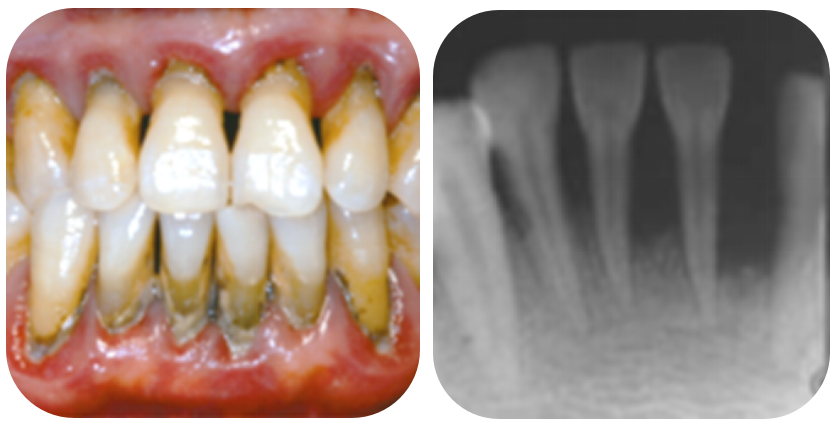

晚期牙周炎:牙齿松动、移位。此时牙槽骨吸收严重,牙齿松动明显,牙周治疗为时已晚,不仅费用高,并且效果欠佳,严重的牙槽骨吸收还会影响后续镶牙或种牙的效果。